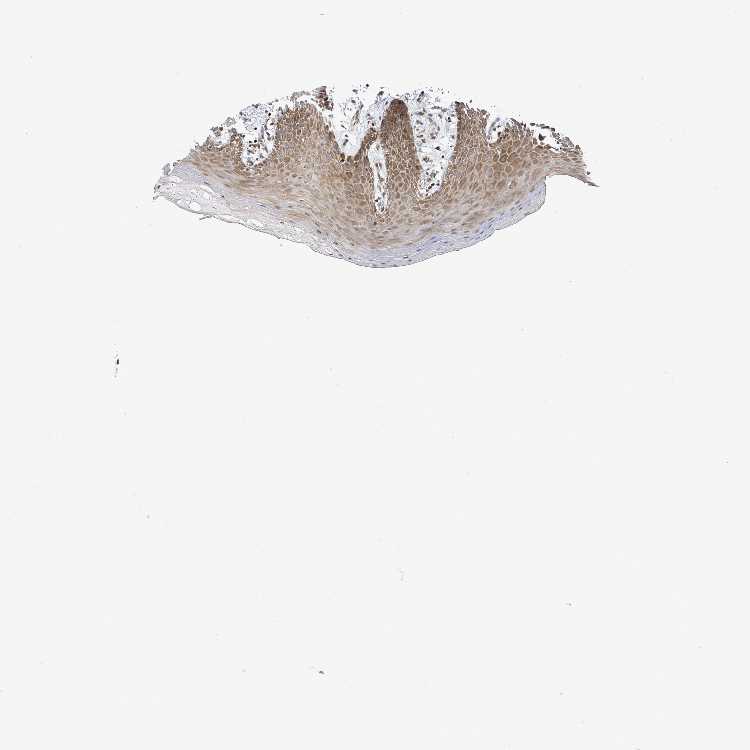

TISSUE PRIMARY DATA ORAL MUCOSA Show tissue menu

Oral mucosa

ORAL MUCOSA - Antibody stainingi

Antibody staining in the annotated cell types in the current human tissue is reported as not detected, low, medium, or high, based on conventional immunohistochemistry profiling in selected tissues. This score is based on the combination of the staining intensity and fraction of stained cells.

Each image is clickable and will lead to virtual microscopy that enables deeper exploration of all samples and also displays staining intensity scores, fraction scores and subcellular localization as well as patient and tissue information for each sample.

Antibody HPA051804Antibody HPA063581

Squamous epithelial cells MediumNot detected